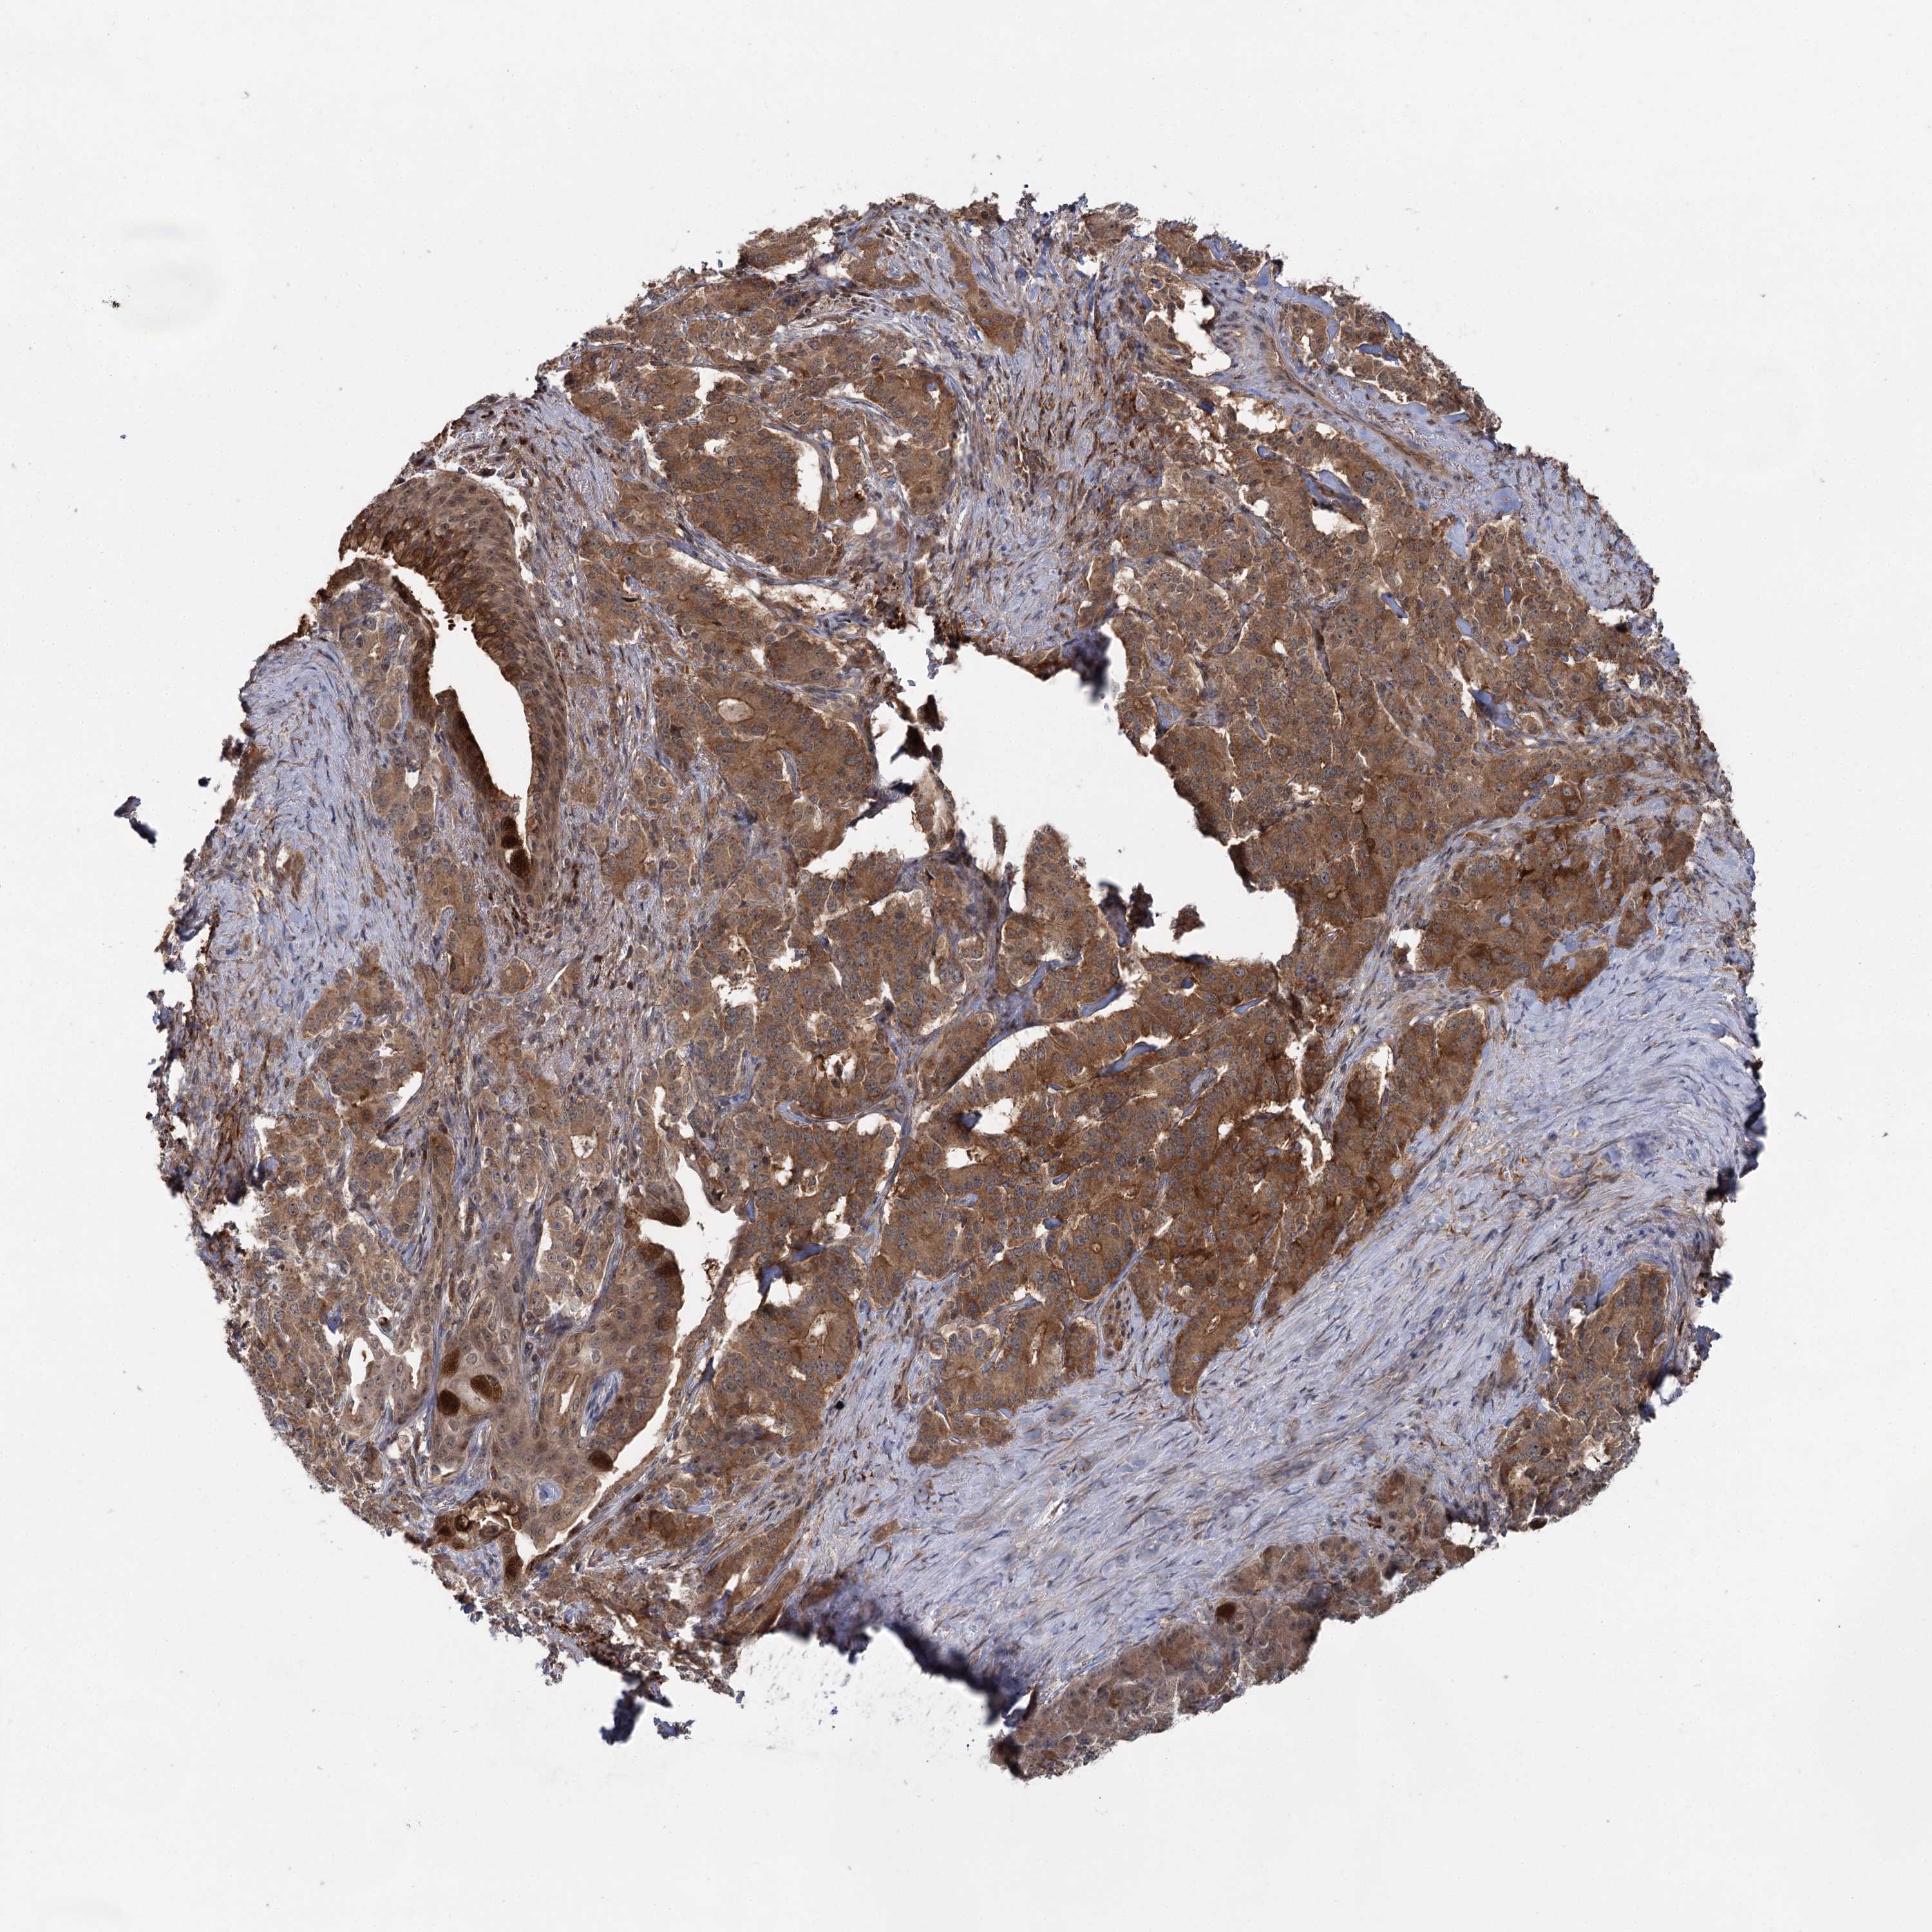

PANCREATIC CANCER - Protein expressioni

A mouse-over function shows sample information and annotation data. Click on an image to view it in a full screen mode. Samples can be filtered based on level of antibody staining by selecting one or several of the following categories: high, medium, low and not detected. The assay and annotation is described here.

Note that samples used for immunohistochemistry by the Human Protein Atlas do not correspond to samples in the TCGA dataset.

Antibody stainingi

Antibody staining in the annotated cell types in the current human tissue is reported as not detected, low, medium, or high, based on conventional immunohistochemistry profiling in selected tissues. This score is based on the combination of the staining intensity and fraction of stained cells.

Each image is clickable and will lead to virtual microscopy that enables deeper exploration of all samples and also displays staining intensity scores, fraction scores and subcellular localization as well as patient and tissue information for each sample.

Antibody HPA038084

Staining

High

Medium

Low

Not detected

Intensity

Strong

Moderate

Weak

Negative

Quantity

>75%

75%-25%

<25%

None

Location

Nuclear

Cytoplasmic/membranous

Cytoplasmic/membranous,nuclear

Adenocarcinoma, NOS